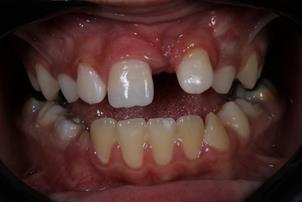

An 8-year-old male patient attended the Emergency Children's Dental Care at the Children's Specialties Clinic-Baby-Clinic of the State University of Londrina, for immediate treatment after a fracture in the right upper central incisor due to a fall during a school sports activity. On intraoral physical examination, a coronal fracture of the enamel and dentin was diagnosed without involvement of the pulp tissue (Figure 1). Response to the vertical and horizontal percussion test was not suggestive of endodontic and periodontal alterations, respectively, and impairment of the periodontal insertion was also ruled out through the mobility test in the buccal-palatal direction.On radiographic examination (Figure 2) confirmed the absence of periodontal and periapical involvement, as well as the absence of root fracture.